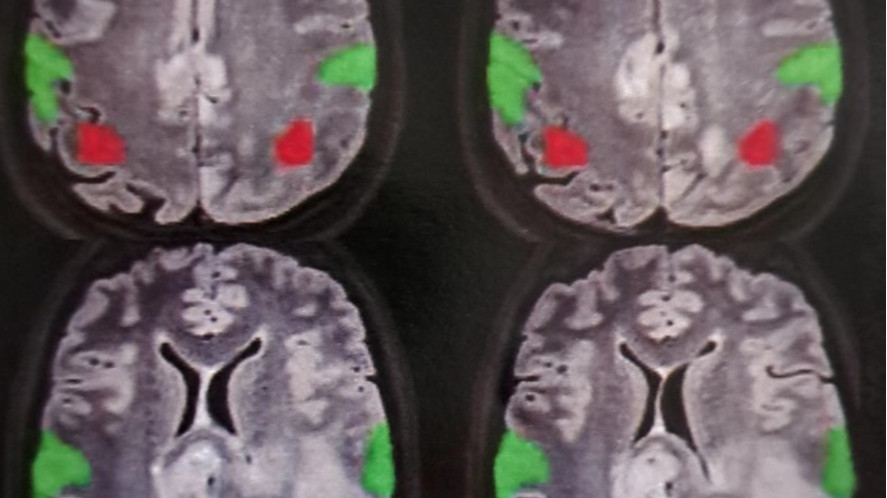

Wyniki badania histopatologicznego były bezlitosne: glejak (glioblastoma). To jeden z najbardziej złośliwych, agresywnych i nieprzewidywalnych nowotworów mózgu. Nawet przy pełnym leczeniu – operacji, radioterapii i chemioterapii – medycyna nie daje żadnych szans na pełne wyleczenie.

Choroba bardzo szybko postępuje. Aneta w przeciągu 3 miesięcy z powodu ucisku 3 guzów na ośrodki mózgu utraciła zdolność pisania i czytania, ma problemy z mową. Cała prawa strona ciała jest bez czucia, nie słyszy na prawe ucho, traci wzrok w prawym oku, nie ma czucia w prawej ręce, a prawa noga jest bezwładna. Sama już się nie porusza i musi jeździć na wózku.